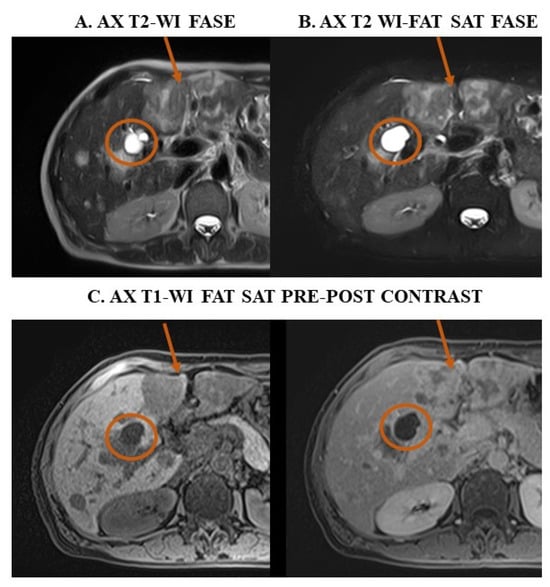

4.1. The Use of MRI to Reduce Radiation Exposure in Oncology Patients